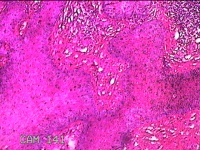

右侧头皮息肉

性别

男

年龄

46岁

临床诊断

一般病史

发现右侧头皮息肉2年余。

标本名称

大体所见

带皮肤组织2x1.2x0.8cm一块,表面光滑,切面灰白粉红色,质中。